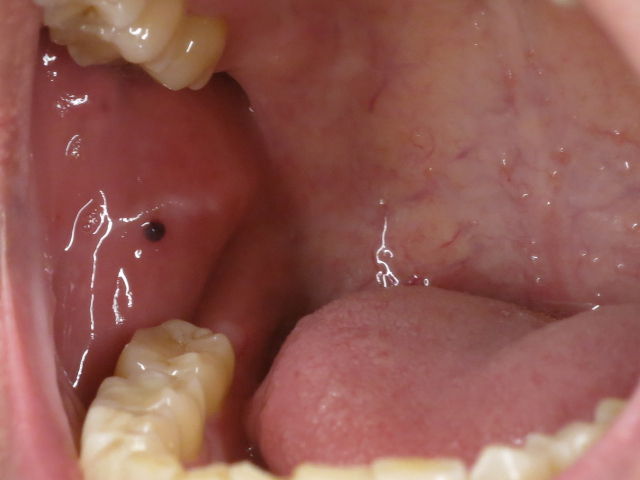

これらのメラニン色素沈着やメタルタトゥーは腫瘍のように膨隆する事や違和感を感じる事もほとんどなく、鏡で見て初めて気が付く事がほとんどです。

これは口腔内の頬粘膜や口唇を湿潤した状態を保つための小さな唾液腺の管の部分が、噛んだり傷ついたりすることによって詰まってしまい、唾液腺体に粘液がたまったもので、透明な膨らみを持ったおでき状のものです。 ポイツ-ジェガース症候群 手、足、口腔粘膜の多発性色素斑と、胃腸にポリープを生じるまれな優性遺伝性疾患です。 また、この場合、どこのお医者さんに診てもらえばよろしいでしょうか?耳鼻咽喉科でしょうか?それともほかの科でしょうか? ご回答、お待ちしています。

あまりない事ではありませすが、口の血豆にはこういった可能性もあるという事を覚えておいてください。 その間にあざが出来たので(肩とかにも数個)かかりつけ医に診てもらったところ よく分からないけどアレルギー性の. 食事ではビタミンBやビタミンCなどをバランスよく摂ることを意識し、自然治癒力を高めていきましょう。 メラニン色素沈着やメタルタトゥーは歯肉に見られる事が比較的多く 形態も円形ではなく不正な形をしており境界もやや不明瞭ですが悪性黒色腫のように治療が必要とはなりません。